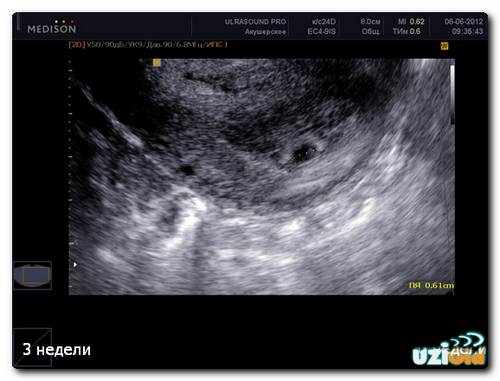

УЗД на 1 тижні вагітності

Фахівці не призначають УЗД під час першого тижня вагітності, так як сам факт зміни положення жінки ще не підтверджений. Жінка навіть не буде здогадуватися про такому маленькому терміні. Про вагітність як про становище говорять вже після 3-го тижня і УЗД може її підтвердити починаючи з цього терміну.

При відчутті деяких змін в організмі, можна звернутися до лікаря-гінеколога для призначення УЗД. На такому терміні УЗД вже здатна підтвердити наявність плода всередині матки.